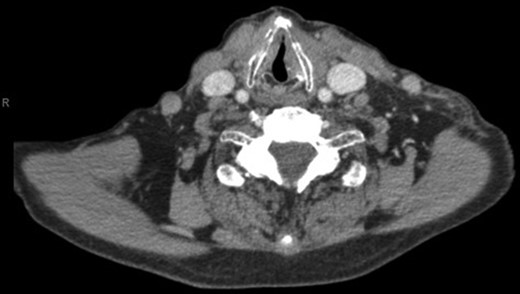

With a working differential of parapharyngeal space infection and possible malignancy, the patient was referred for a computed tomography (CT) scan of the neck and thorax with contrast. The patient was also started empirically on intravenous co-amoxiclav as treatment for neck space collection. CT imaging, performed 24 h after admission, revealed no evidence of malignancy or indeed any paraphayrngeal space collection. Few small lymph nodes were noted on the left side of the neck, but were deemed to be reactive in nature, and left vocal cord palsy was evident (Fig. 1). The key finding was that of a left sternoclavicular joint collection and closely associated superficial anterior chest wall, soft tissue swelling and oedema (Fig. 2). This inflammatory process was also noted deep to the manubrium and sternum and extending somewhat into the mediastinum with evident enlarged mediastinal lymph nodes (Fig. 3). The CT findings were in keeping with SSA with associated superficial and deep tissue inflammation and oedema. With no other cause found, the vocal cord palsy was attributed to the inflammation within the mediastinum, which in turn was caused by superficial burn from hot water bottle use.

Computed tomography. A 67-year-old male with SSA. Findings: soft tissue oedema of the chest seen retrosternally (marker A) and superficially on the left anterior chest (marker B) as well as evidence of mediastinal lymph node enlargement. Technique: contrast-enhanced axial CT of the neck and thorax.